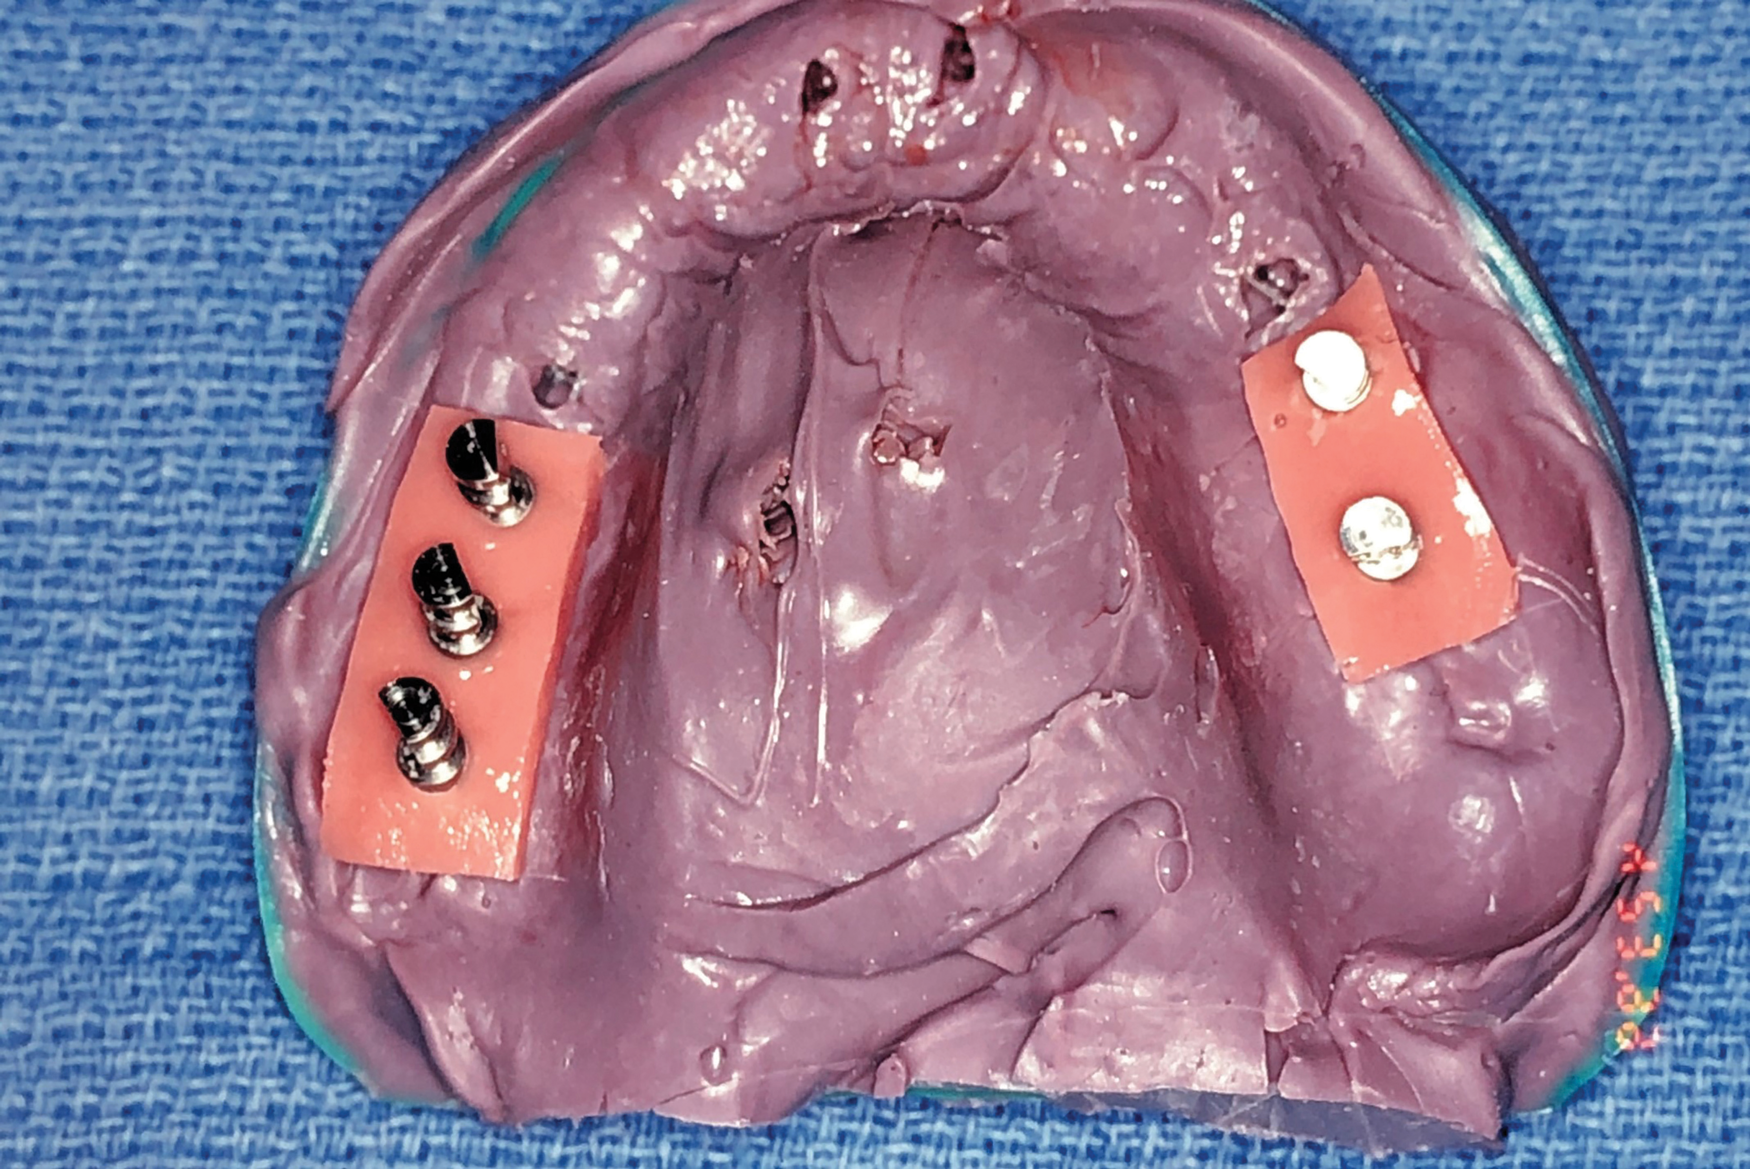

Fig 9. Impression with soft-tissue material for final provisional prosthesis.

Figure 9

Three weeks later (Figure 8), an impression was taken (Figure 9) for a laboratory-processed, screw-retained, implant-supported provisional prosthesis. Six months later, the TIs on sites Nos. 5, 8, 9, and 12 were removed, and two implants (Biomet 3i, 3.25 mm x 13 mm) were placed in sites Nos. 8 and 10 using a surgical guide. Cover screws were then placed (Figure 10). The fixed laboratory-fabricated provisional prosthesis was screwed in on implants Nos. 2, 3, 4, 13, and 14 (Figure 11). After 4 months, the patient presented with uneventful healing, and second-stage surgery was performed on implants Nos. 6, 8, 10, and 11 (Figure 12).